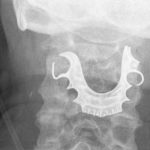

Hombre de 72 años vive con una dentadura postiza atorada en la garganta

La dentadura postiza de un británico de 72 años permaneció durante más de una semana atascada en su garganta luego de que el hombre...